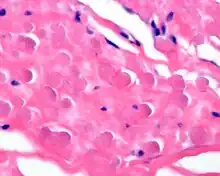

By microscopie view, there is an admixture of heavy dense bands of collagenous tissue dissected by fat and abnormal elastic fibers. The elastic fibers are often quite large and are easily identified. The elastic fibers are coarse, thick, and darkly eosinophilic, often fragmented into globules, creating a "string of pearls" or "pipe cleaner" appearance. Because of degeneration, the elastic fibers will appear as globules with a serrated or "prickled" edge.[4]

The elastic fibers will be highlighted by a Weigert or von Gieson elastic stains.[8]